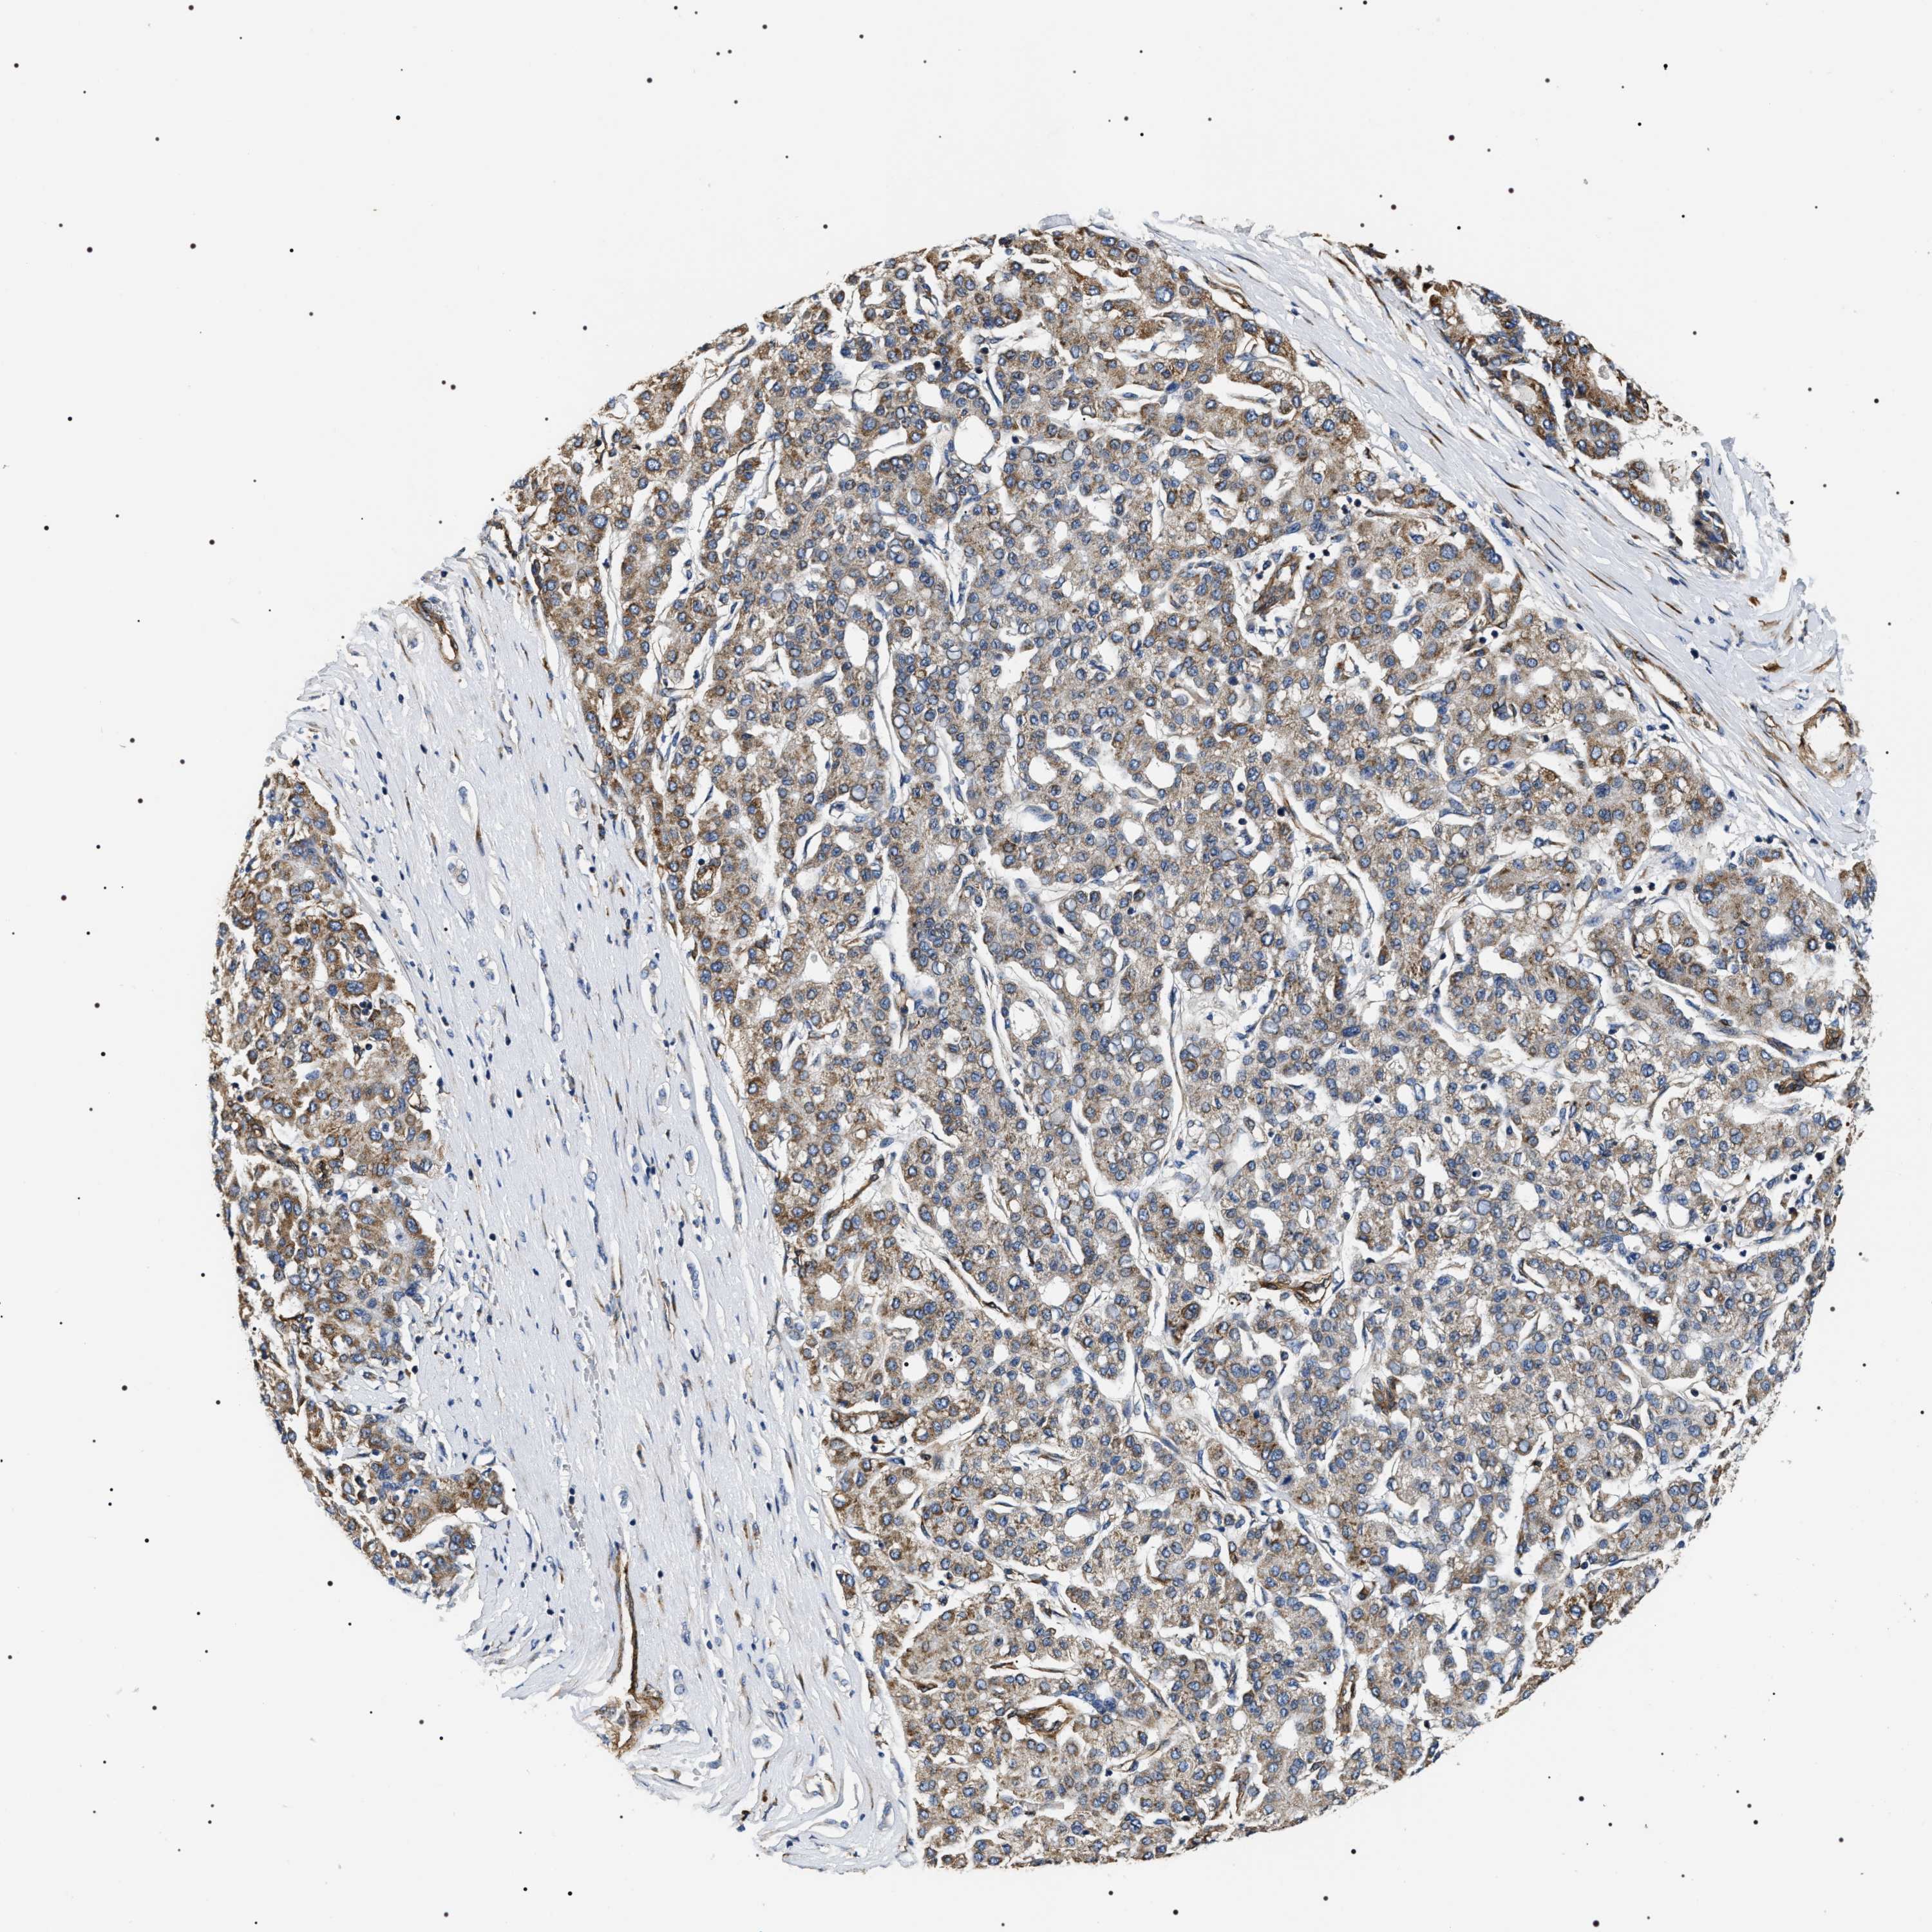

LIVER CANCER - Protein expressioni

A mouse-over function shows sample information and annotation data. Click on an image to view it in a full screen mode. Samples can be filtered based on level of antibody staining by selecting one or several of the following categories: high, medium, low and not detected. The assay and annotation is described here.

Note that samples used for immunohistochemistry by the Human Protein Atlas do not correspond to samples in the TCGA dataset.

Antibody stainingi

Antibody staining in the annotated cell types in the current human tissue is reported as not detected, low, medium, or high, based on conventional immunohistochemistry profiling in selected tissues. This score is based on the combination of the staining intensity and fraction of stained cells.

Each image is clickable and will lead to virtual microscopy that enables deeper exploration of all samples and also displays staining intensity scores, fraction scores and subcellular localization as well as patient and tissue information for each sample.

Antibody HPA020386

Staining

High

Medium

Low

Not detected

Intensity

Strong

Moderate

Weak

Negative

Quantity

>75%

75%-25%

<25%

None

Location

Nuclear

Cytoplasmic/membranous

Cytoplasmic/membranous,nuclear

Cholangiocarcinoma

Carcinoma, Hepatocellular, NOS